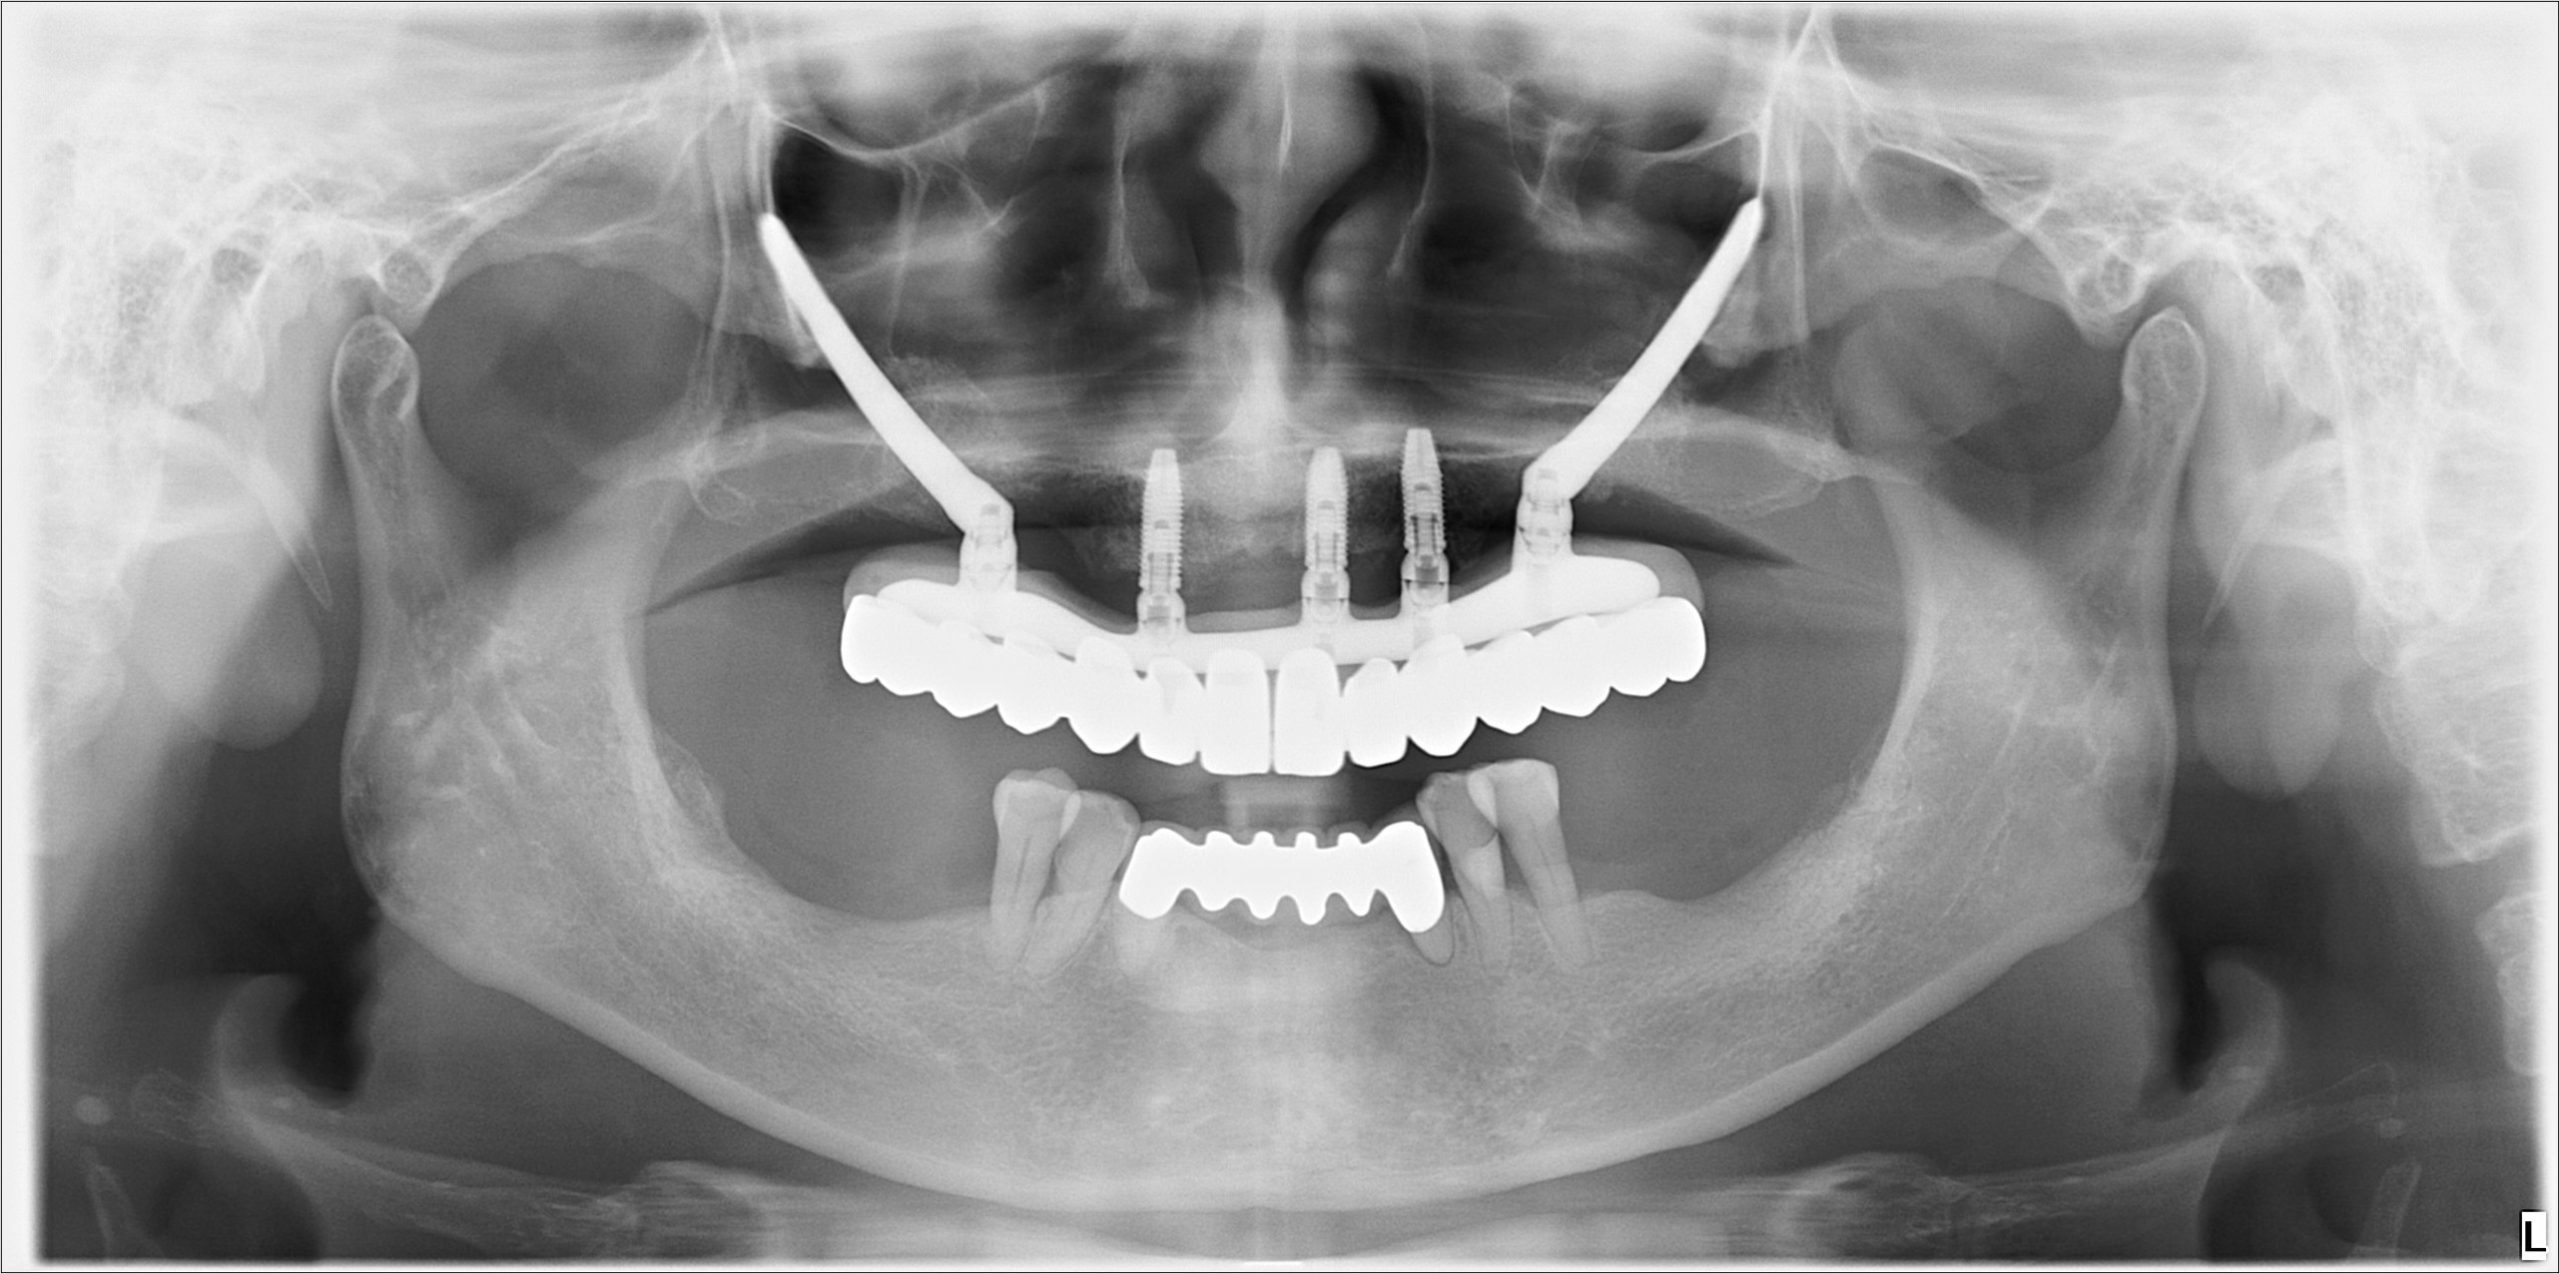

▍上顎裝戴正式假牙

▍正式假牙術後Pano